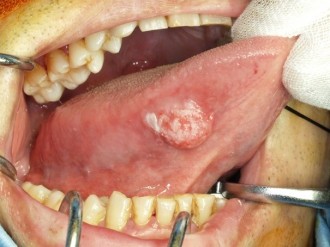

癌の発生する部位や病期(癌の進行度)によって様々です。癌表面の特徴としては、ぶつぶつしていたり、赤や白色に変色している、かたい腫瘤(こぶのような盛り上がり)や潰瘍(えぐれたような形態)を形成していることがあり、時に簡単に出血したり痛みが出ることもあります。病気が進むにつれて噛みにくさや飲み込みにくさ、発音のしにくさが出てきたり、頸部(くび)のリンパ節への転移、遠隔転移(肺、骨、肝臓等)を生じるようになります。

舌癌